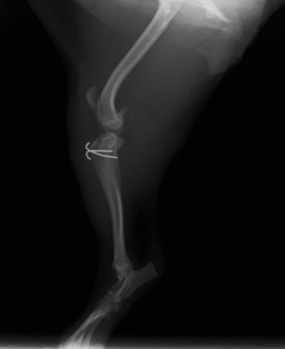

■ 症例22 ポメラニアン 1歳5か月 去勢雄

左後肢の挙上を主訴に来院した。整形学的検査、レントゲン検査より左右の膝蓋骨脱臼(左GradeⅡ〜Ⅲ、右Grade Ⅱ)を認めた。また、脛骨の前方引き出し試験の際に、引き出し兆候は認められないものの、疼痛が認められたため、前十字靭帯の損傷が疑われた。術中における、目視および関節内の操作によって、前十字靭帯の損傷や過伸展といった異常が認められなかったため、膝蓋骨脱臼の整復のみ実施した。手術手技は縫工筋及び内側広筋の解放、脛骨粗面の外側転位、滑車ブロック形造溝術、内外側関節包の縫縮を実施した。本症例は跛行もなく経過良好である。しかし、頸骨高平部の角度(TPA)が 右26.2°、左24.9°であり、解剖学的に前十字靭帯損傷のリスクが高いことから今後の経過に注意が必要である。